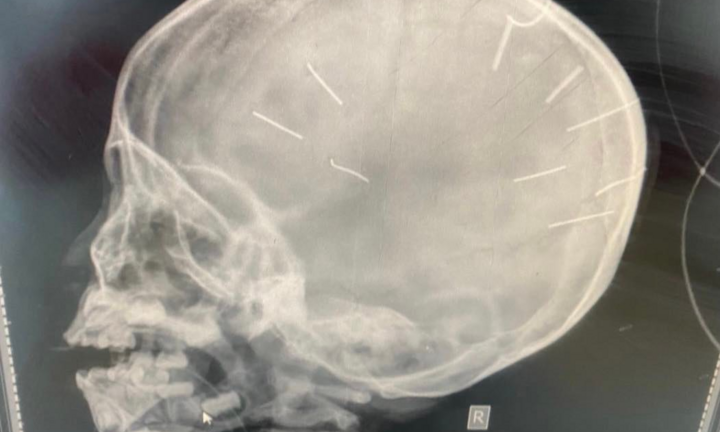

Tình trạng bé gái 3 tuổi có đinh trong sọ vẫn rất nặng

Đại diện Bệnh viện Đa khoa Xanh Pôn (Hà Nội) thông tin về sức khỏe bé gái 3 tuổi có đinh trong hộp sọ.